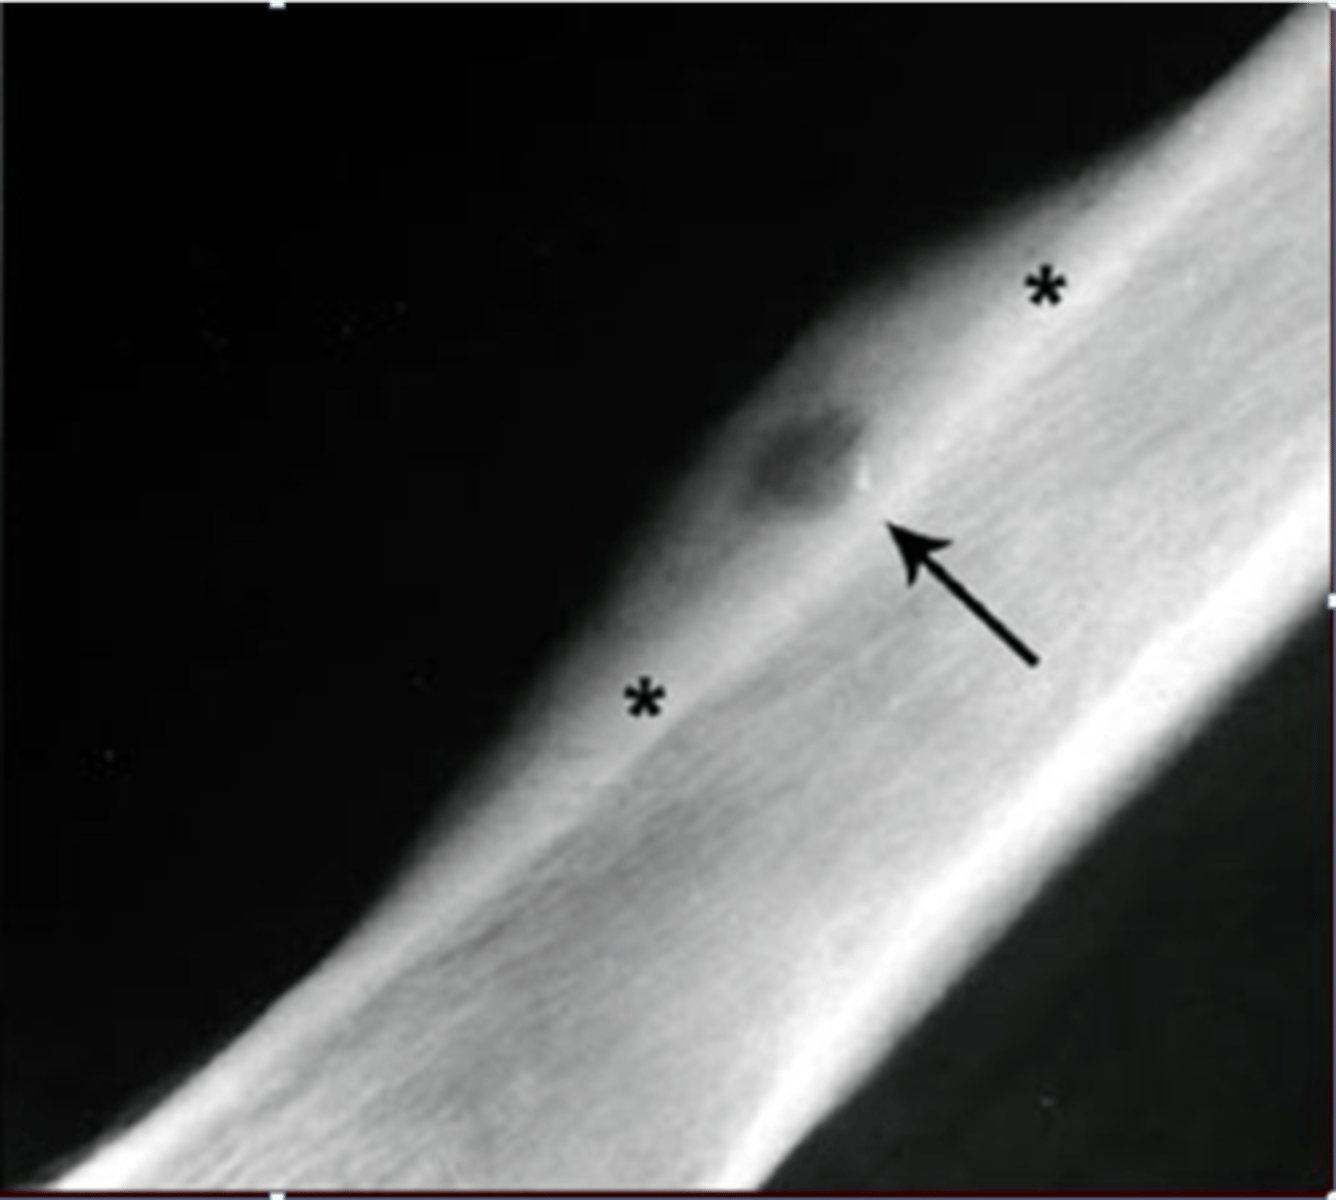

Geographic bone blister

ID radiographic feature of non-ossifying fibroma indicated by top arrow

Septations

ID radiographic feature of non-ossifying fibroma indicated by bottom arrow

Pathologic fracture

Non-ossifying fibroma with _____